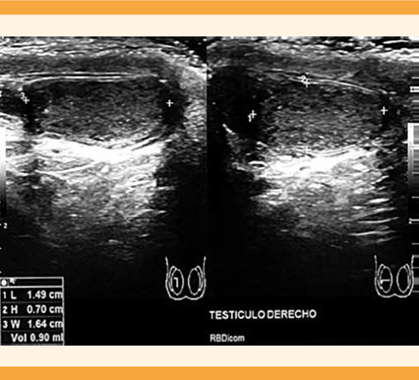

A la pareja se le practicaron estudios de laboratorio y gabinete. A la paciente se le solicitó progesterona, prolactina y hormona estimulante de tiroides (TSH) tomados en fase lútea media que indicaron ovulación, prolactinemia normal y eutiroidismo. La histerosalpingografía reportó que la cavidad uterina se encontraba normal y las salpinges permeables. Al varón se le solicitó un análisis seminal que reportó azoospermia; se repitió a las 2 semanas y nuevamente se encontró azoospermia, con un espermocultivo en búsqueda de Chlamydia y Mycoplasma que se reportó negativo. El semen se centrifugó para confirmar el diagnóstico de azoospermia. Los siguientes estudios se enfocaron en conocer la causa de la azoospermia y poder iniciar un tratamiento adecuado. El ultrasonido testicular reportó ambos testículos disminuidos de tamaño con contornos regulares, derecho 1.4 x 0.7 x 1.6 cm con volumen de 0.9 cc (Figura 1), izquierdo 1.6 x 1.5 x 0.8 cm con volumen de 1.1 cc (Figura 2). Epidídimos hipoecoicos con un quiste en la cabeza, en el lado derecho de 1.7 mm. Ambos cordones espermáticas sin flujo Doppler y disminución en su ecogenicidad.

Figura 1 Imagen de ultrasonido testicular derecho, se observan los cortes longitudinal y transversal y el volumen testicular con hipotrofia.